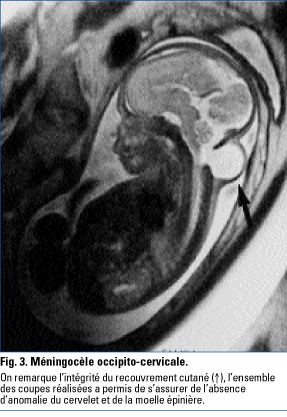

L'imagerie par résonance magnétique foeœtale - Revue Médicale Suisse